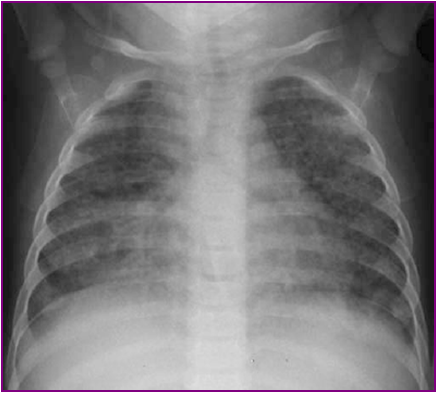

急性粟粒性肺结核

急性血行播散型肺结核

Acute miliary pulmonary tuberculosis